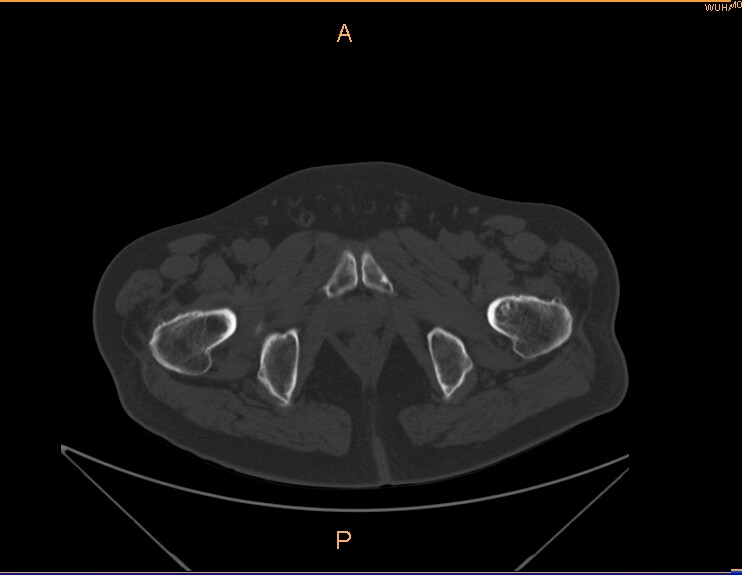

标题: CT29088:左股骨颈 [打印本页]

标题: CT29088:左股骨颈

左侧股骨颈疼痛。

左股骨颈软骨瘤可能,建议增强或mri

内生软骨瘤。

不排除骨样骨瘤

不排除左侧股骨颈内生软骨瘤可能。

内生软骨瘤年龄较小,分叶状,局部皮质有改变,钙化为环形半环形,没有这么粗大。

左股骨颈软骨瘤可能,建议增强或mri  。